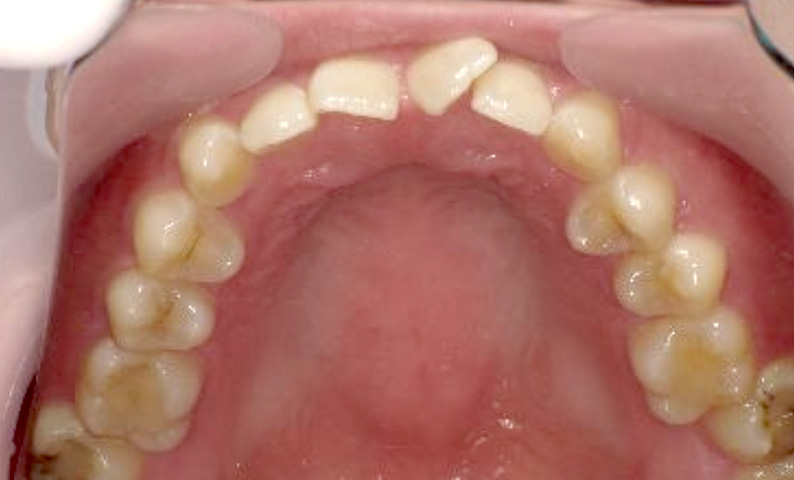

症例_005 上下顎の部分矯正

治療期間:11ヶ月金額:54万円+税女性前歯のガタガタ捻転歯

| Before | After |